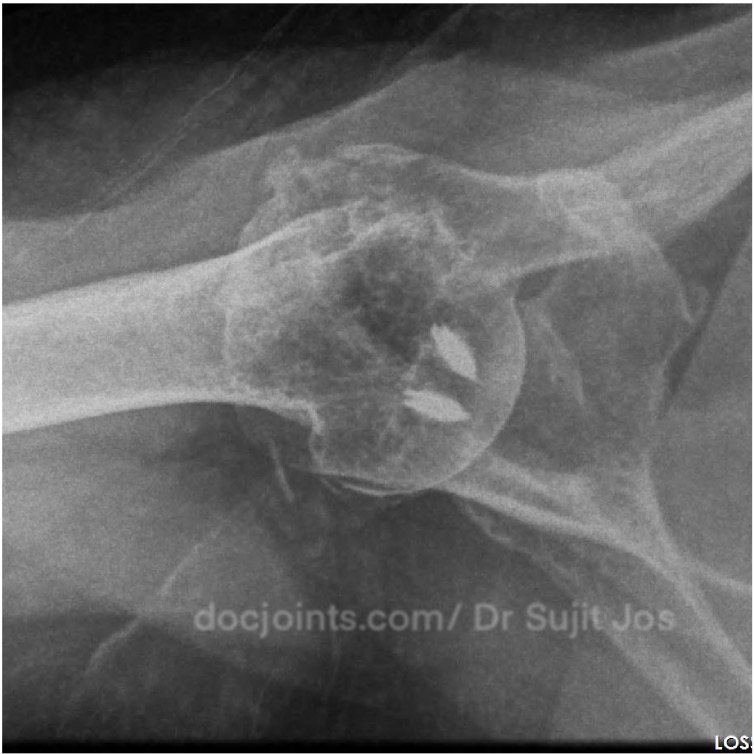

Re Retear of Rotator cuff repair done elsewhere. Failed Rotator Cuff Repair Managed with Reverse Shoulder Arthroplasty

For nearly two years, she had been struggling with persistent shoulder pain. Simple daily activities — combing her hair, dressing, even sleeping — had become difficult. She had already undergone two surgeries for her shoulder at another center, hoping each time that things would finally improve.

The tendon in her shoulder was severely damaged and no longer repairable. Repeating the same type of surgery again would not help her.

At this stage, we discussed the available options with her. Considering her age, the condition of the joint, and her previous surgeries, we recommended a reverse shoulder replacement — a procedure designed to restore function even when the tendons are no longer working.